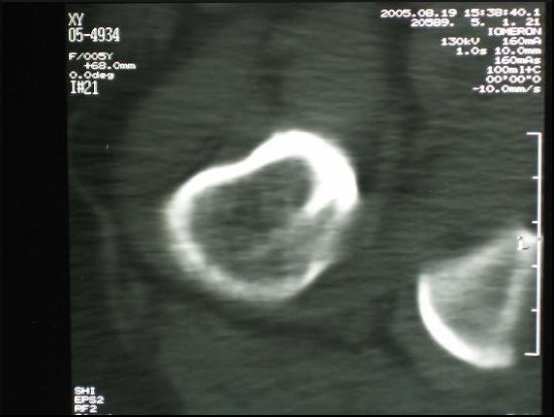

Dobierając skład chemiczny i strukturę materiału kompozytowego, z którego wykonujemy modele przeznaczone do szkoleń, główny nacisk położyliśmy na dokładne odtworzenie właściwości naturalnej kości. W tym celu poddaliśmy kość różnorodnym badaniom. Tą samą technikę zastosowaliśmy badając modele z materiałów kompozytowych.